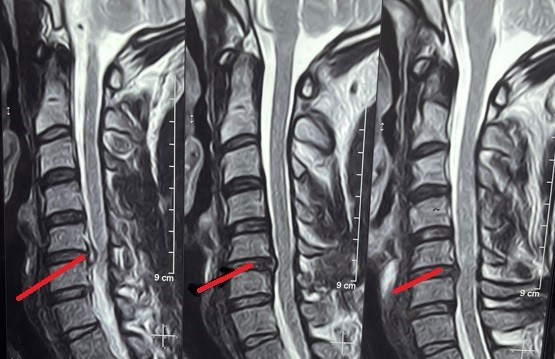

unilevel cervical herniated disc

Magnetic resonance imaging (MRI) of a 52-year-old female patient suffering from weakness and partial upper extremity weakness due to a herniated cervical disc between the fifth and sixth cervical vertebrae. As shown in red, the location of the slip and the size of the effect resulting from pressure on the cervical spinal cord and nerve roots. And the image shaded in green after a surgical microscope surgery to remove the cartilage from the front and install a cervical cage or an alternative anterior cervical brace, three months after the surgery.